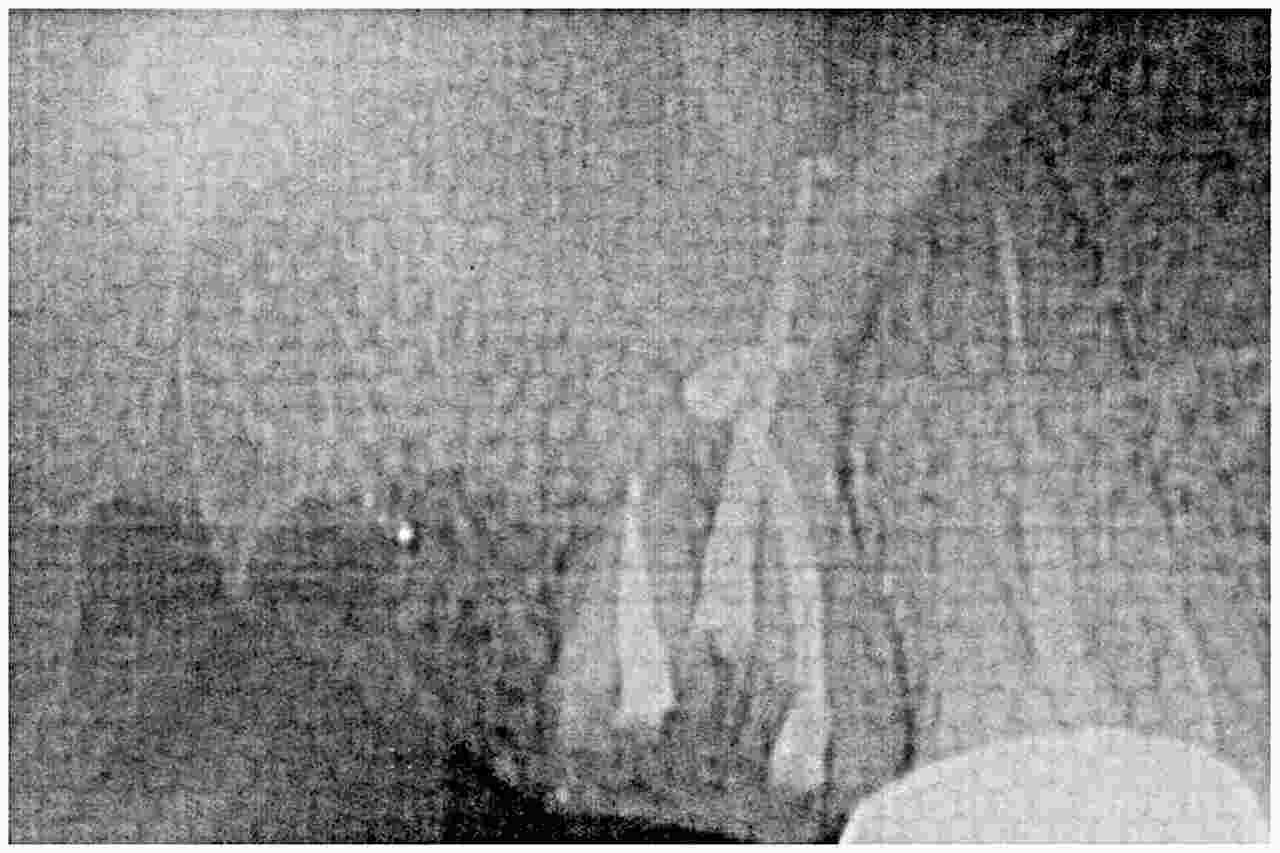

7番を根充後のデンタルレントゲンになります

6番も根の治療を行っていきます